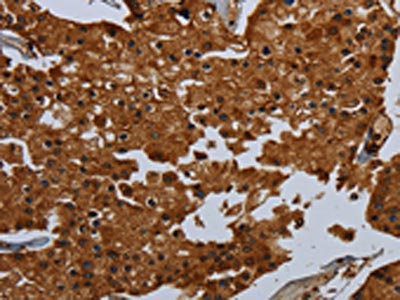

The image on the left is immunohistochemistry of paraffin-embedded Human prostate cancer tissue using CSB-PA886215(ENTPD7 Antibody) at dilution 1/60, on the right is treated with fusion protein. (Original magnification: ×200)